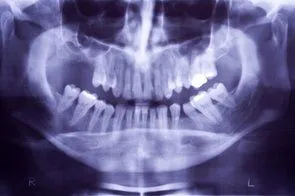

Sinus Augmentation

Loss of posterior teeth may result in excessive forces being placed on your remaining teeth. Fortunately, the use of dental implants and crowns allow you to replace these missing teeth. However, the position of the sinus in the upper posterior areas may be too low for proper placement of dental implants.

A simple procedure allows the sinus floor to be repositioned, creating enough space to properly place an implant. Various grafting materials are used to encourage your bone to grow more quickly into the area, helping to stabilize the dental implant. Replace with your own bone in this area the grafting material as it grows into the area.

Under certain conditions, an even simpler procedure can be utilized. When possible, the bone remaining under the sinus floor is gently “pushed up”, thus lifting the floor of the “dropped” sinus. Bone replacement materials are then placed beneath this lifted bone. Once again the bone materials are replaced as your body grow new bone into this area.

Sinus augmentation procedures are highly predictable, with studies reporting over 95% success. Following sufficient healing of a sinus augmentation (6-10 months), implants are placed in a predictable and successful manner. It is important to realize that if the sinus augmentation procedure does not result in enough bone for implant placement, additional bone may be regenerated through a second sinus augmentation procedure at the time of implant placement.